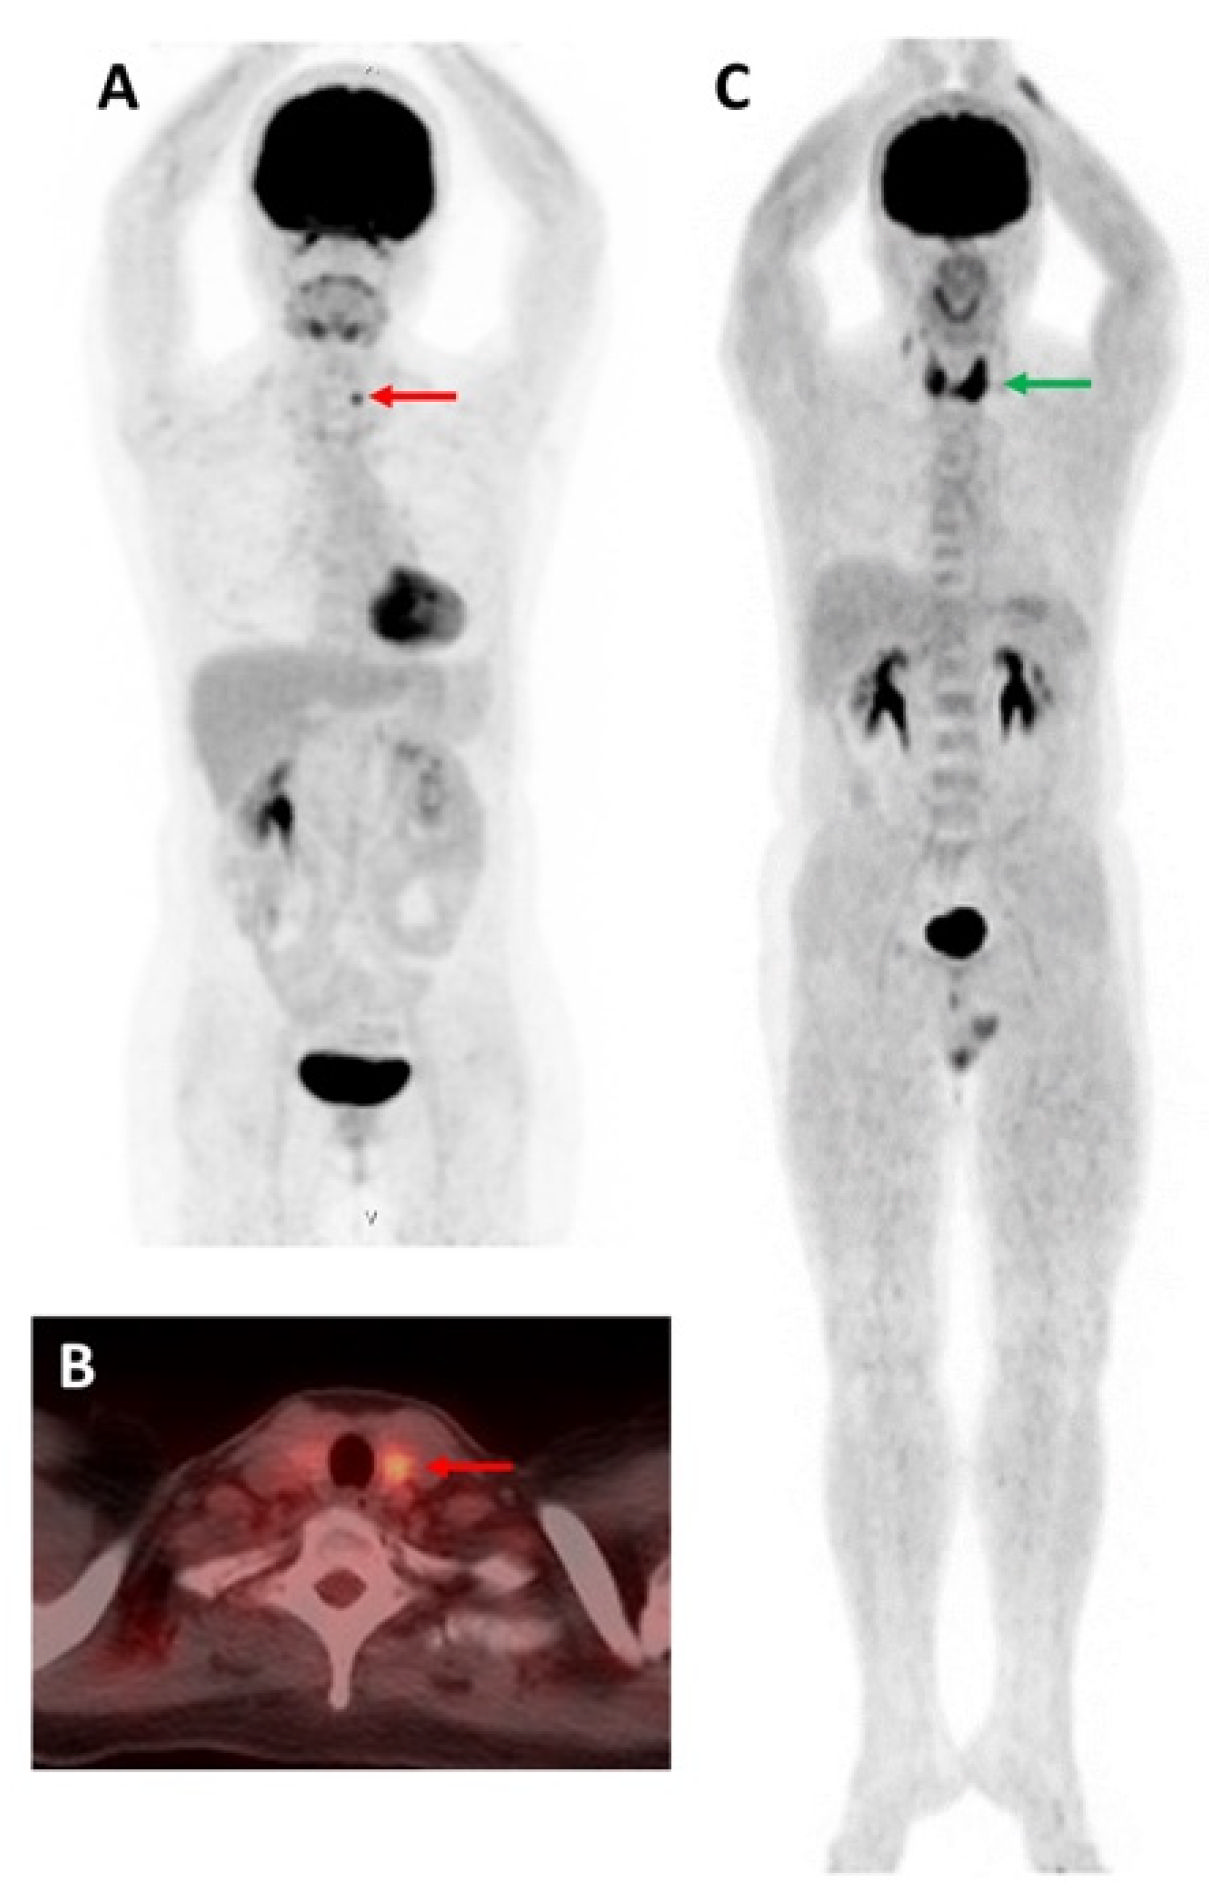

- De Vries, L.H.; Lodewijk, L.; Braat, A.J.A.T.; Krijger, G.C.; Valk, G.D.; Lam, M.G.E.H.; Borel Rinkes, I.H.M.; Vriens, M.R.; de Keizer, B. 68Ga-PSMA PET/CT in Radioactive Iodine-Refractory Differentiated Thyroid Cancer and First Treatment Results with 177Lu-PSMA-617. EJNMMI Res. 2020, 10, 18. [Google Scholar] [CrossRef]